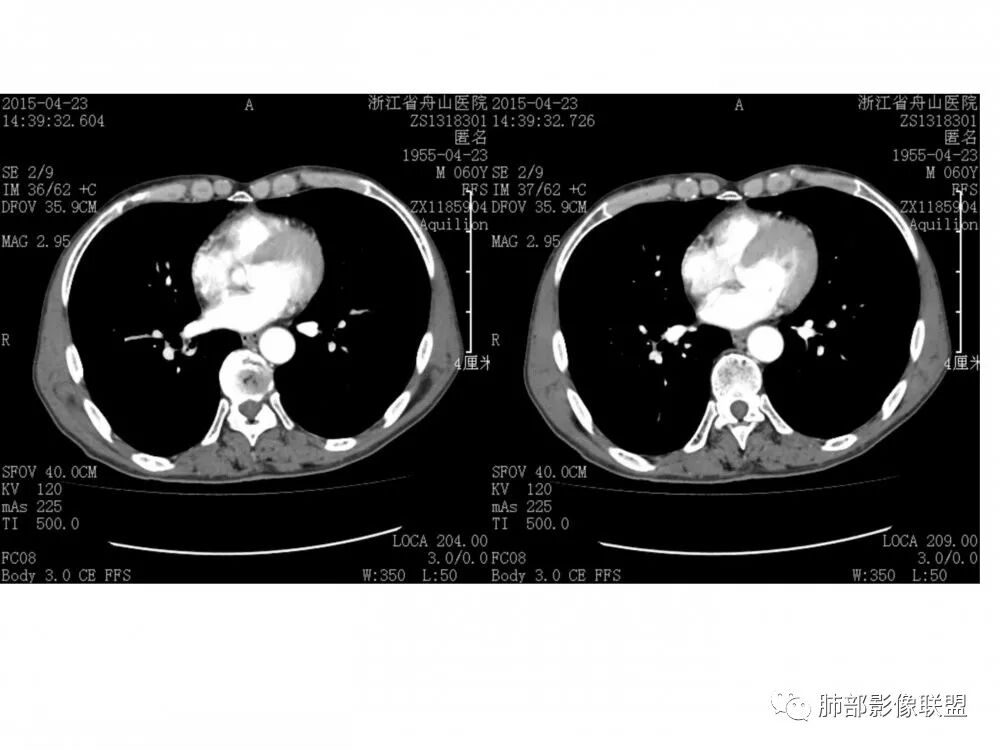

右肺下叶支气管开口新生物,轴位管腔及纵向基底干大部分受累狭窄,支气管管壁破坏并突破形成腔外肿块,血管累及变细,肉眼观轻度强化,右肺门、纵膈淋巴结肿大,恶性没问题,阻塞性炎症不明显,类癌强化明显不支持,老年男性,首先考虑小细胞癌,鉴别不典型鳞癌和腺癌。

右肺下叶支气管内新生物,破坏管壁向腔外膨胀生长,累及各基底段开口,无明显坏死,有局部强化,远端无明显阻塞,右肺门及纵隔淋巴结肿大,考虑恶性可能大,对临床来说,非常简单,纤支镜直接取病理活检就完事了,但病理分型对影像来说就比较纠结了,小细胞?类癌?粘表?腺样囊腺癌?低分化腺癌?鳞癌?只有暂时把小细胞考虑到前面,其他待排,等纤支镜活检确定。

右肺下叶开口支气管内新生物,破坏管壁向腔外膨胀生长,累及各基底段开口,无明显坏死,有局部强化,远端无明显阻塞,右肺门及纵隔淋巴结肿大,考虑恶性肿瘤。大气道肿瘤不支持腺癌。小细胞癌大多为周围病灶引起肺门、纵隔淋巴结转移,肺门淋巴结明显肿大后侵犯支气管粘膜到达支气管内(从外到内),本例病灶从管腔内向腔外长,不支持小细胞癌。病灶为轻→中度强化,类癌显著强化为主→不支持,鳞癌、腺样囊性癌一般中度强化,鳞癌大多有阻塞性病变,本例无明显阻塞不支持鳞癌。粘液表皮样癌一般为轻度不均匀强化。感觉病灶为轻中度不均匀强化。综上首先考虑粘表,其次腺样囊性癌。待支气管镜活检明确。

病理结果:鳞癌